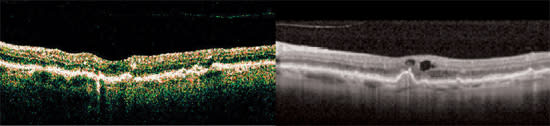

The scans shown here illustrate the utility of spectral domain OCT for imaging a range of pathology (Figures 1–3).

Figure 1. A 79-year-old man with new onset blurred vision and distortions is diagnosed with age-related macular degeneration. Time domain OCT (left) failed to demonstrate clear signs of exudation, but spectral domain OCT (right) reveals retinal thickening and intraretinal cystoid spaces.